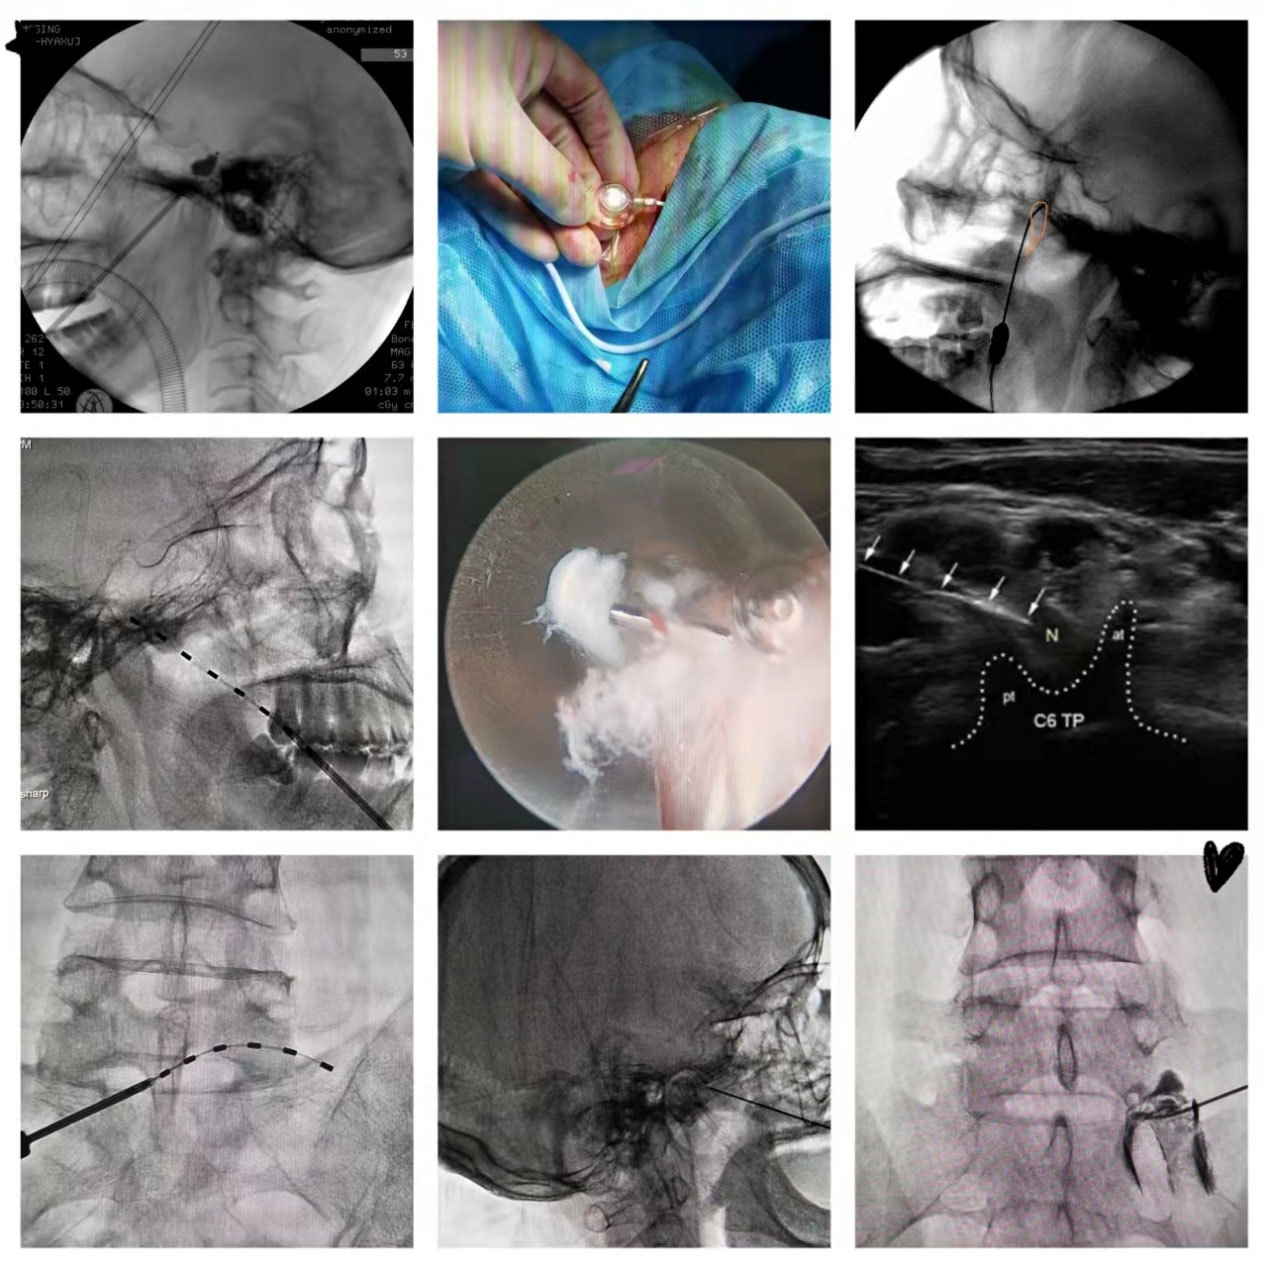

疼痛科成立于2013年9月,科室坚持 “以患者为中心,以满意为标准”的服务宗旨,“以影像引导微创介入技术”为强科理念,紧跟疼痛医学发展前沿,传播疼痛知识、普及疼痛诊疗技术;围绕卫健委2016版《三级综合医院医疗服务能力指南》开展疼痛专科治疗技术。根据患者病因和临床特点,与患者、家属共同制定诊疗计划,同各临床科室紧密协作,进行“一站式”综合治疗,为患者提供包括药物治疗、物理治疗、介入治疗、微创手术为一体的阶梯治疗技术。

疼痛科采用各种方法,包括药物、物理治疗和微创手术等方法对疼痛疾病进行完善的综合治疗。特别是影像引导微创介入技术为患者带来最大获益包括:

1、鞘内药物输注系统(港/泵)植入术治疗难治性癌痛;

2、三叉神经半月节球囊压迫术和射频消融术治疗三叉神经痛;

3、标准(脉冲)射频技术治疗各种神经性疼痛;

4、银质针、PRP等治疗各种骨骼肌肉疼痛和损伤;

5、低温等离子消融术治疗椎间盘源性疼痛;

6、内镜技术治疗神经根性疼痛;

7、脊髓神经电刺激治疗带状疱疹后神经痛、顽固性神经病理性疼痛;

8、SPVP技术治疗脊柱肿瘤转移性疼痛;

9、超声、C臂、DSA、CT引导技术,使操作可视化、安全性大为提高。